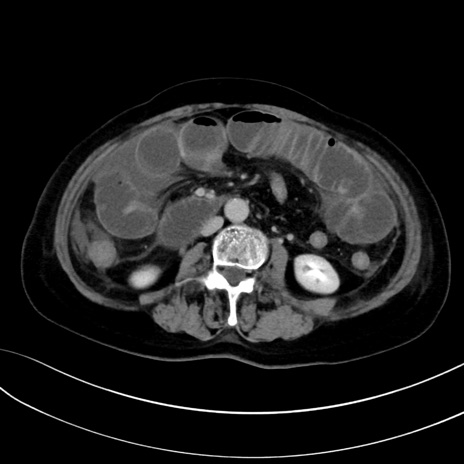

症例13 CT(横断像)1日半後